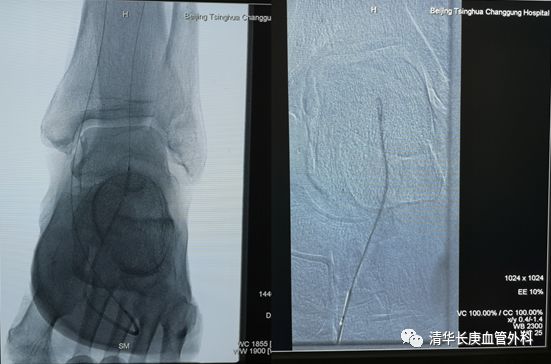

下肢动脉粥样硬化闭塞症、糖尿病足腔内治疗往往充满悬念,完全闭塞严重钙化病变的“遭遇战”极具挑战。张童副主任医师为大家演示了膝上、膝下不同部位的CTO病变突击战,风格迥异:一例胫前动脉CTO病变,通过胫后动脉Loop技术重建足背动脉,在此基础上“接力”逆穿足背末节趾间动脉起始段,方案应变坚决果断,思路出乎意料,入路精准稳定,博得满堂彩。